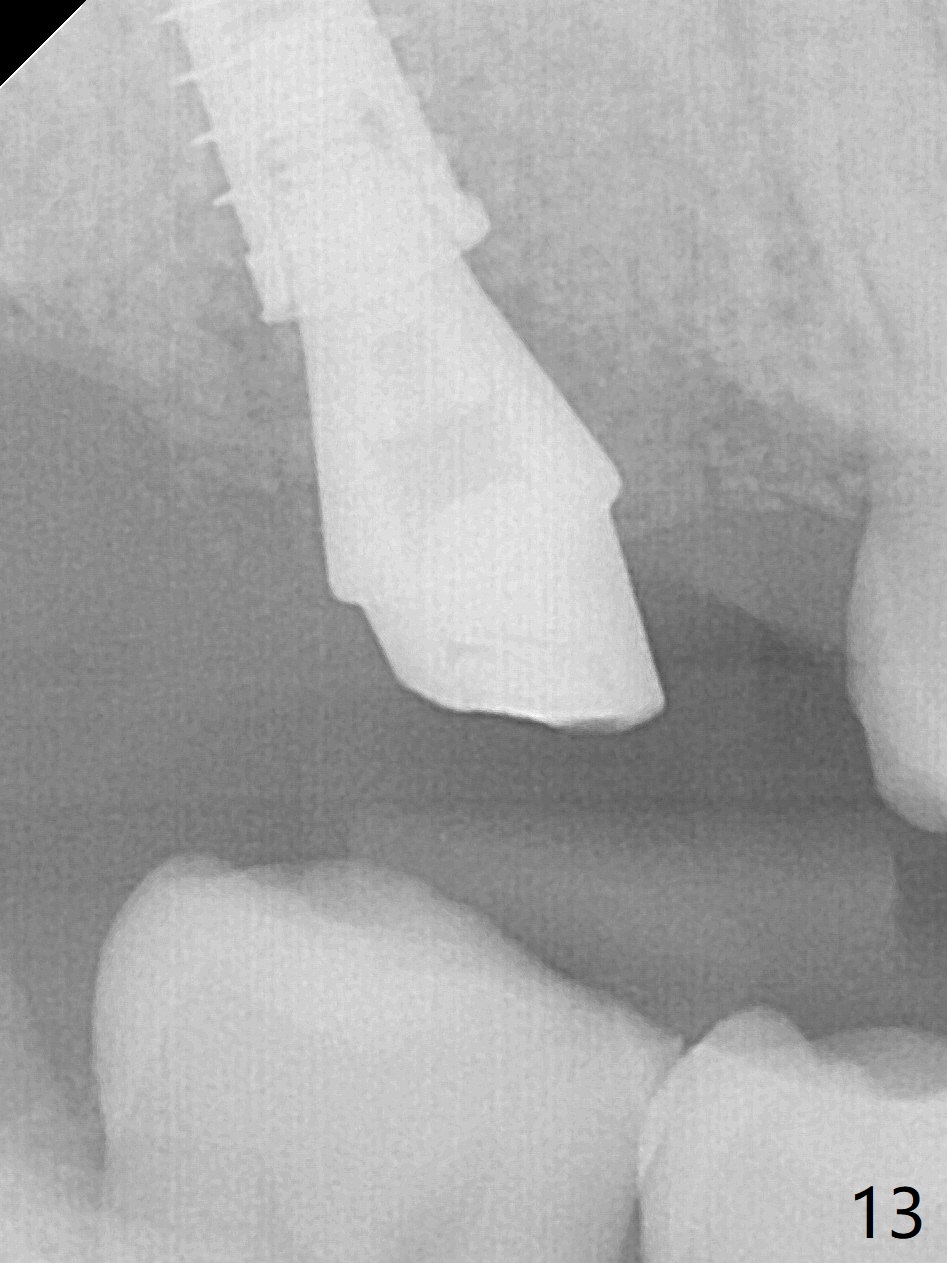

There is a fistula distal to the tooth #2 with deep pocket distopalatally (Fig.1 *), corresponding to palatal root fracture (Fig.2). There is a septum (Fig.3 S) between the buccal (B) and palatal (P) sockets. Osteotomy is initiated in the center of the septum (Fig.4 black circle). In fact the center of the socket is buccal (red circle), in which osteotomy should have been established because of the presence of the distopalatal bony defect associated with the root fracture and the distal fistula. The less ideal initial osteotomy leads to palatal placement of the implant and abutment (Fig.11 vs. 12).

Fig.5 shows the mesial slope of the socket (M), which is more or less the center of the socket mesiodistally. If the osteotomy were set up in the red circle (Fig.6) in the mesial slope (Fig.8 green dashed line), the trajectory of 4.5x11 mm dummy implant (Fig.7) would be more ideal (Fig.8 red outline) with more native bone contact. Finally a longer IBS implant is placed (4.5x15 mm, Fig.9,10) to achieve primary stability (50 Ncm). When the provisional is removed for impression 3 months 10 days postop, the implant is found to have been placed distopalatally (Fig.13), which should have been avoided. It appears essential to use guide for a distal implant. It is agonizing to re-encounter the off-axial implant (Fig.14) and the distopalatal access hole (Fig.15) 1 year post cementation. It is also amazing that the abutment screw has not loosened. A fair-sized piece of bone graft has just been removed buccally (Fig.15,16). The patient complains of sensitivity 2 years 3 months post cementation, although there is no abnormality around the implant crown. Guided surgery is essential to avoid restoration complication. There is no thread exposure nearly 3 years post cementation; in fact the apical portion of the abutment is covered by the bone (Fig.17,18).